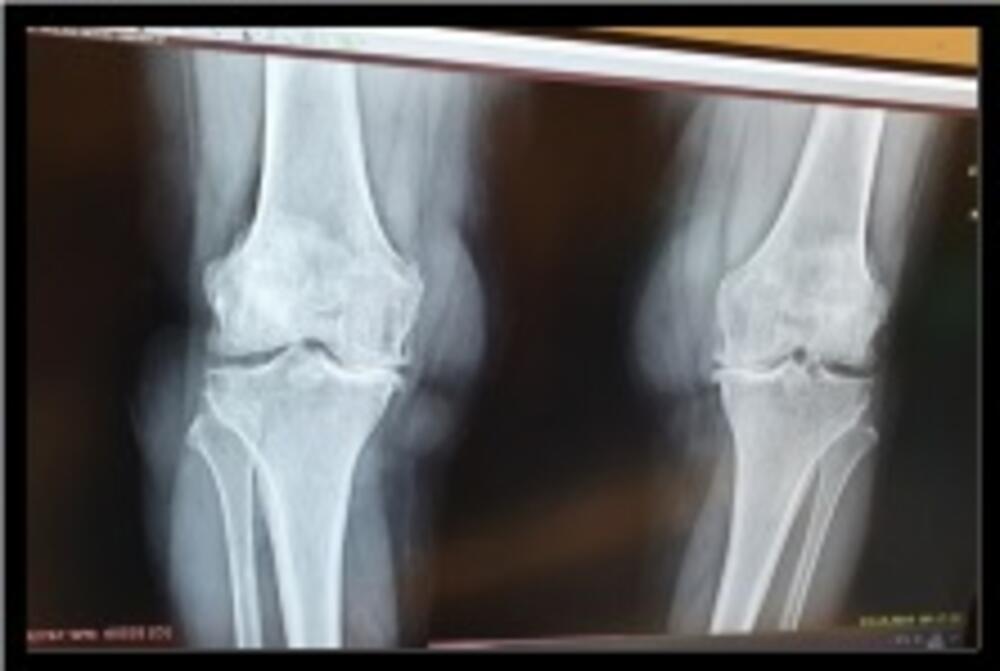

Osteoartroza – gonartroza je oboljenje koje dovodi do destrukcije hrskavice, subhondralne skleroze i formiranja osteofita. U kliničkoj slici gonartroze dominira bol, nestabilnost i otežano kretanje.